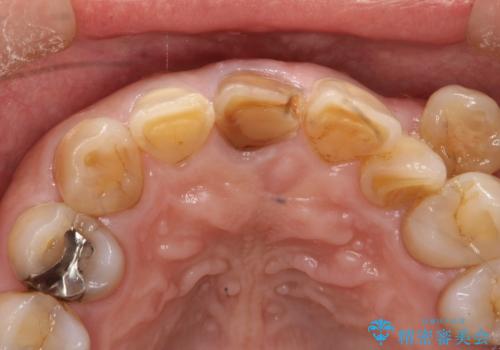

セラミックによる前歯の変色の改善

- 前歯の色が変色してきて、気になるとのことで来院されました。

オールセラミックを装着することで改善することとしました。